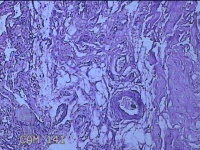

右手掌肿物

性别

女

年龄

32岁

临床诊断

1.右手掌肿物性质待查?右腕管综合征

一般病史

发现右手掌肿物疼痛伴拇示中指感觉迟钝约6年。

标本名称

大体所见

灰白粉红色肿物2.5x2x0.8cm一个,表面光滑,切开肿物呈实性,切面灰白粉红色,质软。